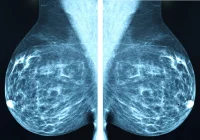

Mammography is the main method for breast cancer screening but is less effective for individuals with dense breast tissue, who have a higher risk of cancer. Contrast-enhanced MRI is more sensitive but expensive and time-consuming. An abbreviated MRI (AB-MR) protocol shows promise in maintaining sensitivity while reducing time and cost. Studies comparing AB-MR to other methods show higher cancer detection rates. However, there's limited data on AB-MR's effectiveness beyond the initial screening round. This study aims to compare the outcomes of baseline and subsequent rounds of AB-MR screening in individuals with dense breasts at average risk of breast cancer.

The AB-MR examinations were performed using various MRI systems and bilateral breast coils, following a specific imaging protocol consisting of axial sequences including STIR, pre-contrast fat-suppressed T1-weighted sequence, and single-timepoint post-contrast T1-weighted sequence. An axial DWI sequence was added to the protocol in a subset of examinations.

The AB-MR studies were interpreted by subspecialty-trained breast radiologists using the ACR BI-RADS MRI lexicon. Biopsy outcomes were assessed for patients with BI-RADS categories 4 or 5, and cancer characteristics were recorded, including cancer stage at diagnosis, histology, receptor status, tumour size, and nodal status.